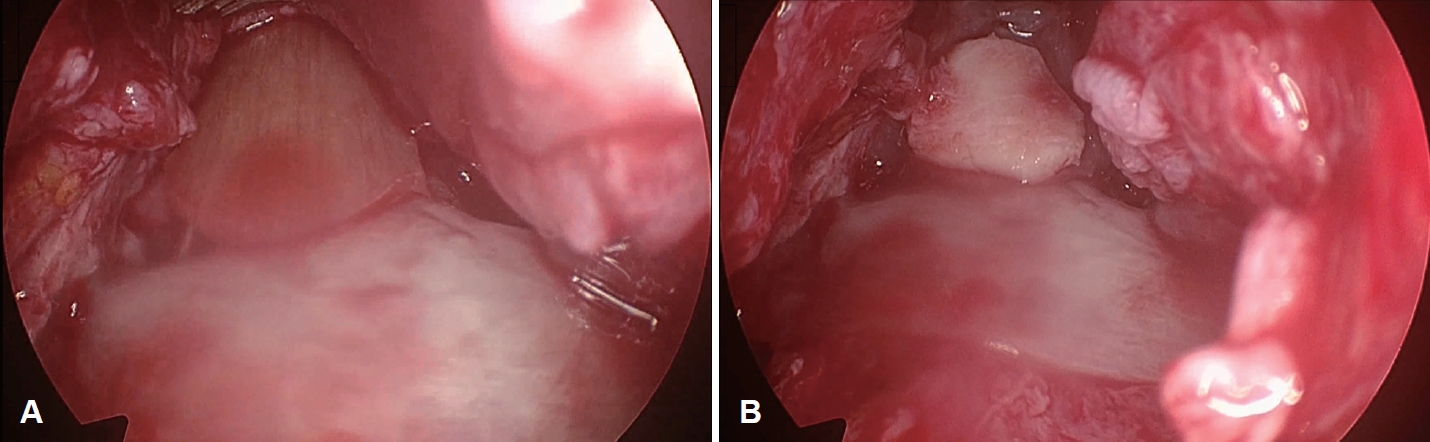

The implant capsule was carefully dissected and debrided. While exposing of the upper lateral cartilages and nasal bones, a small defect on the left nasal bone was found, communicating with the nasal cavity (Fig. 3A). The periosteum was elevated to expose the frontal bone, which showed a defect approximately 1 cm in diameter (Fig. 3A). The defect on the anterior wall of the frontal sinus contained a small amount of granulation tissue but showed no evidence of pus (Fig. 3B). The granulation tissue was subsequently debrided. After its removal, the opening of the frontal sinus wall was identified (Fig. 3C).

Fig. 2.Sagittal CT scan cut showed penetration of anterior table of frontal sinus by a foreign body implant for a rhinoplasty. Fig. 3.Intraoperative endoscopic findings of nasal bone and frontal sinus defects. A: Intraoperative endoscopic view of nasal dorsum showed left nasal bone defect and hole of anterior table of frontal sinus after removal of foreign body implant. B and C: Before debridement of granulation tissue in frontal sinus wall defect (B), after debridement (C). Fig. 4.Reconstruction process of the nasal bone and frontal sinus defects. A: The defects was reconstructed by placing homologous fascia, secured with fibrin glue. B: Ear cartilage har- vested from the right auricular cymba concha, was placed on top of the fascia to reinforce the reconstructed site. REFERENCES1. Winkler AA, Soler ZM, Leong PL, Murphy A, Wang TD, Cook TA. Complications associated with alloplastic implants in rhinoplasty. Arch Facial Plast Surg 2012;14(6):437-41.